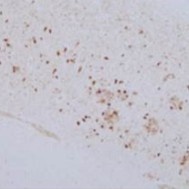

抗りん酸化Tau T181, ラットモノクローナル抗体(2E2-A6)

- 動物種

- ヒト (アルツハイマー病患者)

- 部位

- 海馬CA1

- サンプル

- パラフィン切片

<データ提供>

同志社大学 生命医科学部 医生命システム学科神経病理学 宮坂先生

(所属はデータ提供当時のもの)